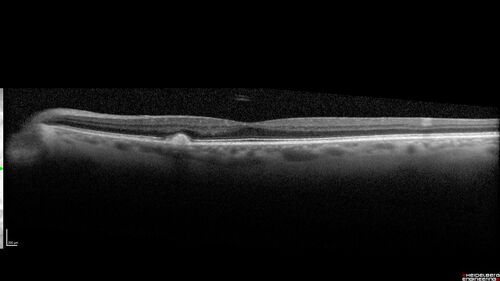

Large Hyper-reflective drusen in age-related macular degeneration

69 year old healthy woman with 20/20 vision and no visual complaints